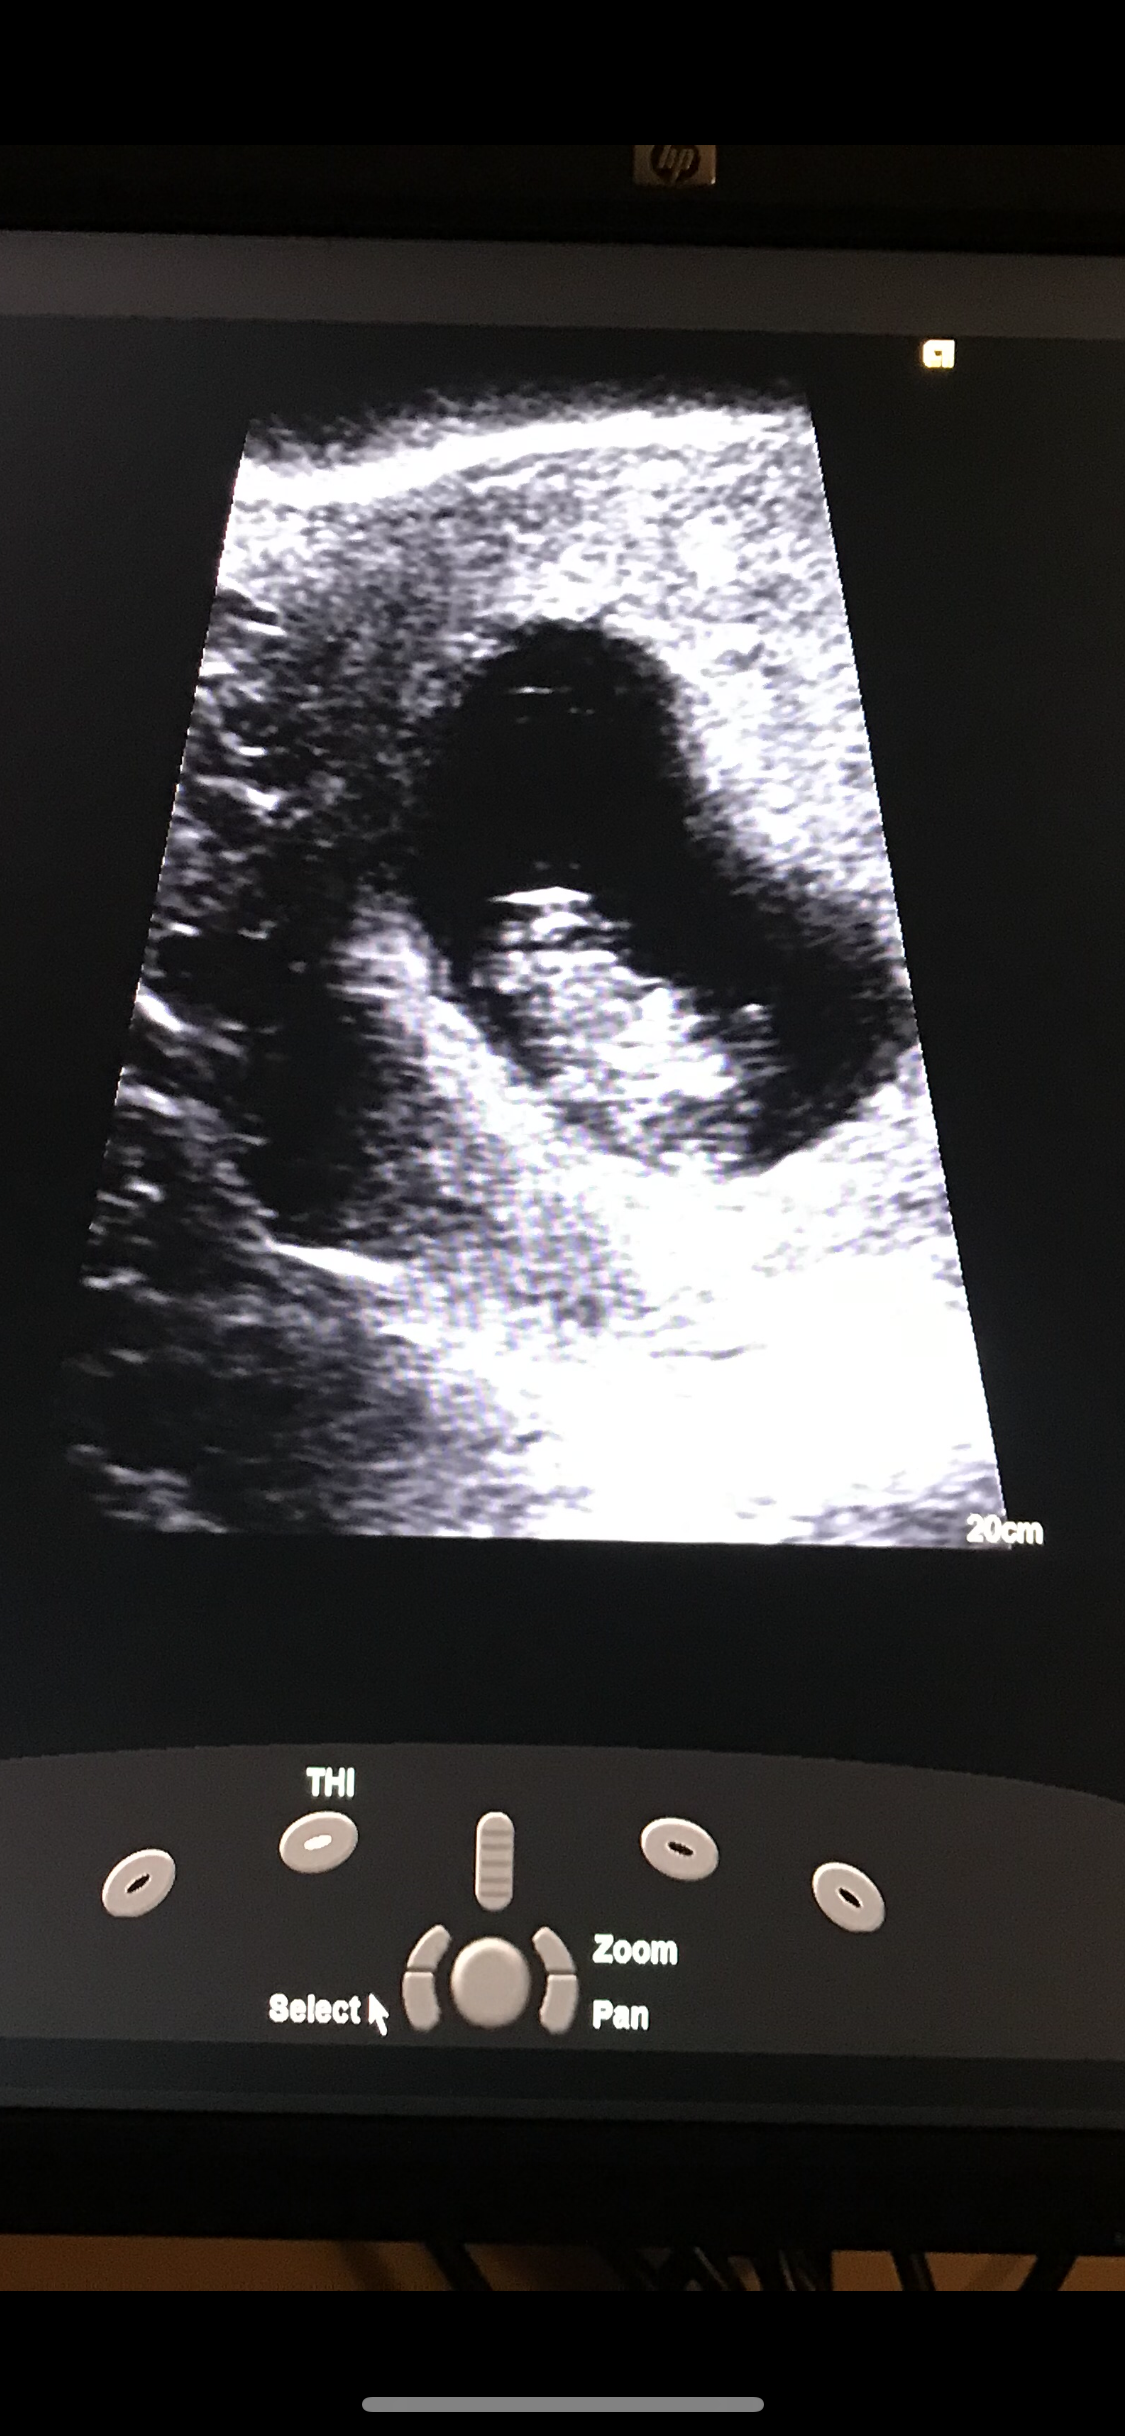

Had another ultrasound Sunday at the ER I was 9w2d and I had pain and bleeding. They found a hemorrhage but baby was doing good HR was 170 and the baby even looks like they’re smiling!